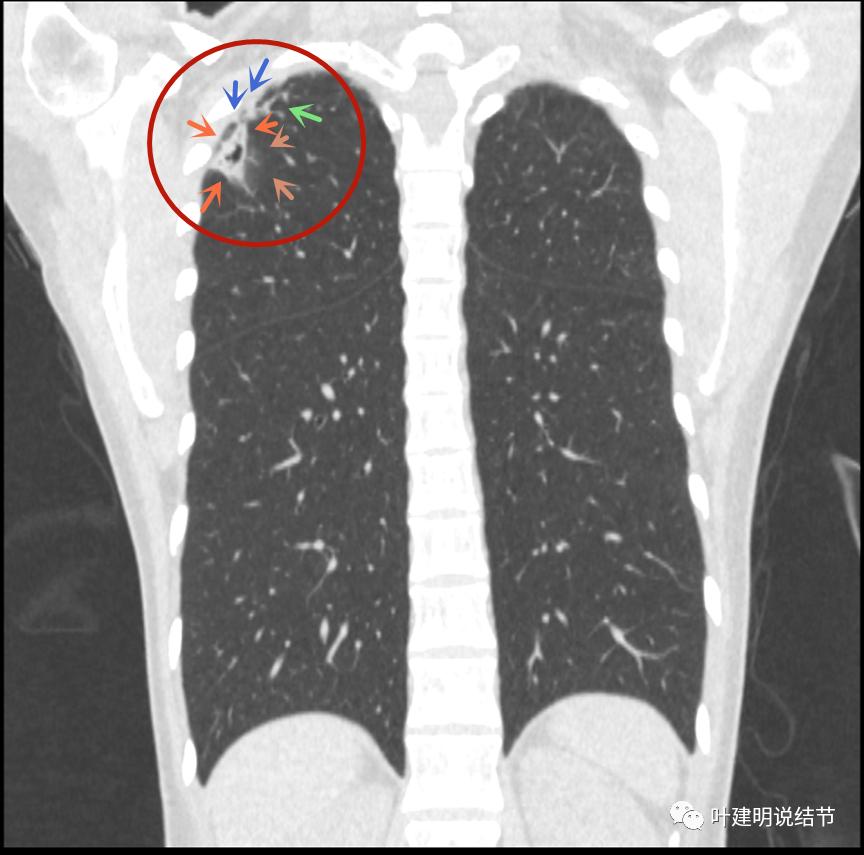

我们再来瞧瞧冠状位与矢状位的图像:

病灶较散,有磨玻璃影,但磨玻璃的边缘模糊不清(砖色箭头),囊壁密度过高(粉色箭头),毛刺样的结构偏长,空洞内壁较光滑,有卫星灶(绿色箭头)

病灶邻近胸膜增厚明显(蓝色箭头);病灶似三角形,边缘平直(桔色箭头);有磨玻璃淡且散,边缘不清(砖色箭头);有卫星病灶(绿色箭头)